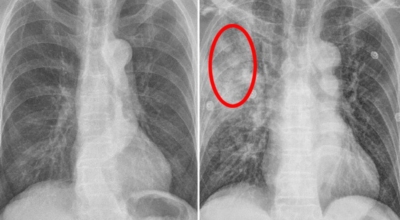

폐암 검사는 X-ray를 통해서 검사하는데 , 크기가 작거나 구석에 위치한 경우 확인이 어려운 경우도 있습니다. 그리고 조직 검사를 통해서 정확한 진단을 하게 되어요. 폐암이 발견되면 종양의 크기나 전이 여부 , 위치에 따라서 수술 여부를 결정하게 돼요.